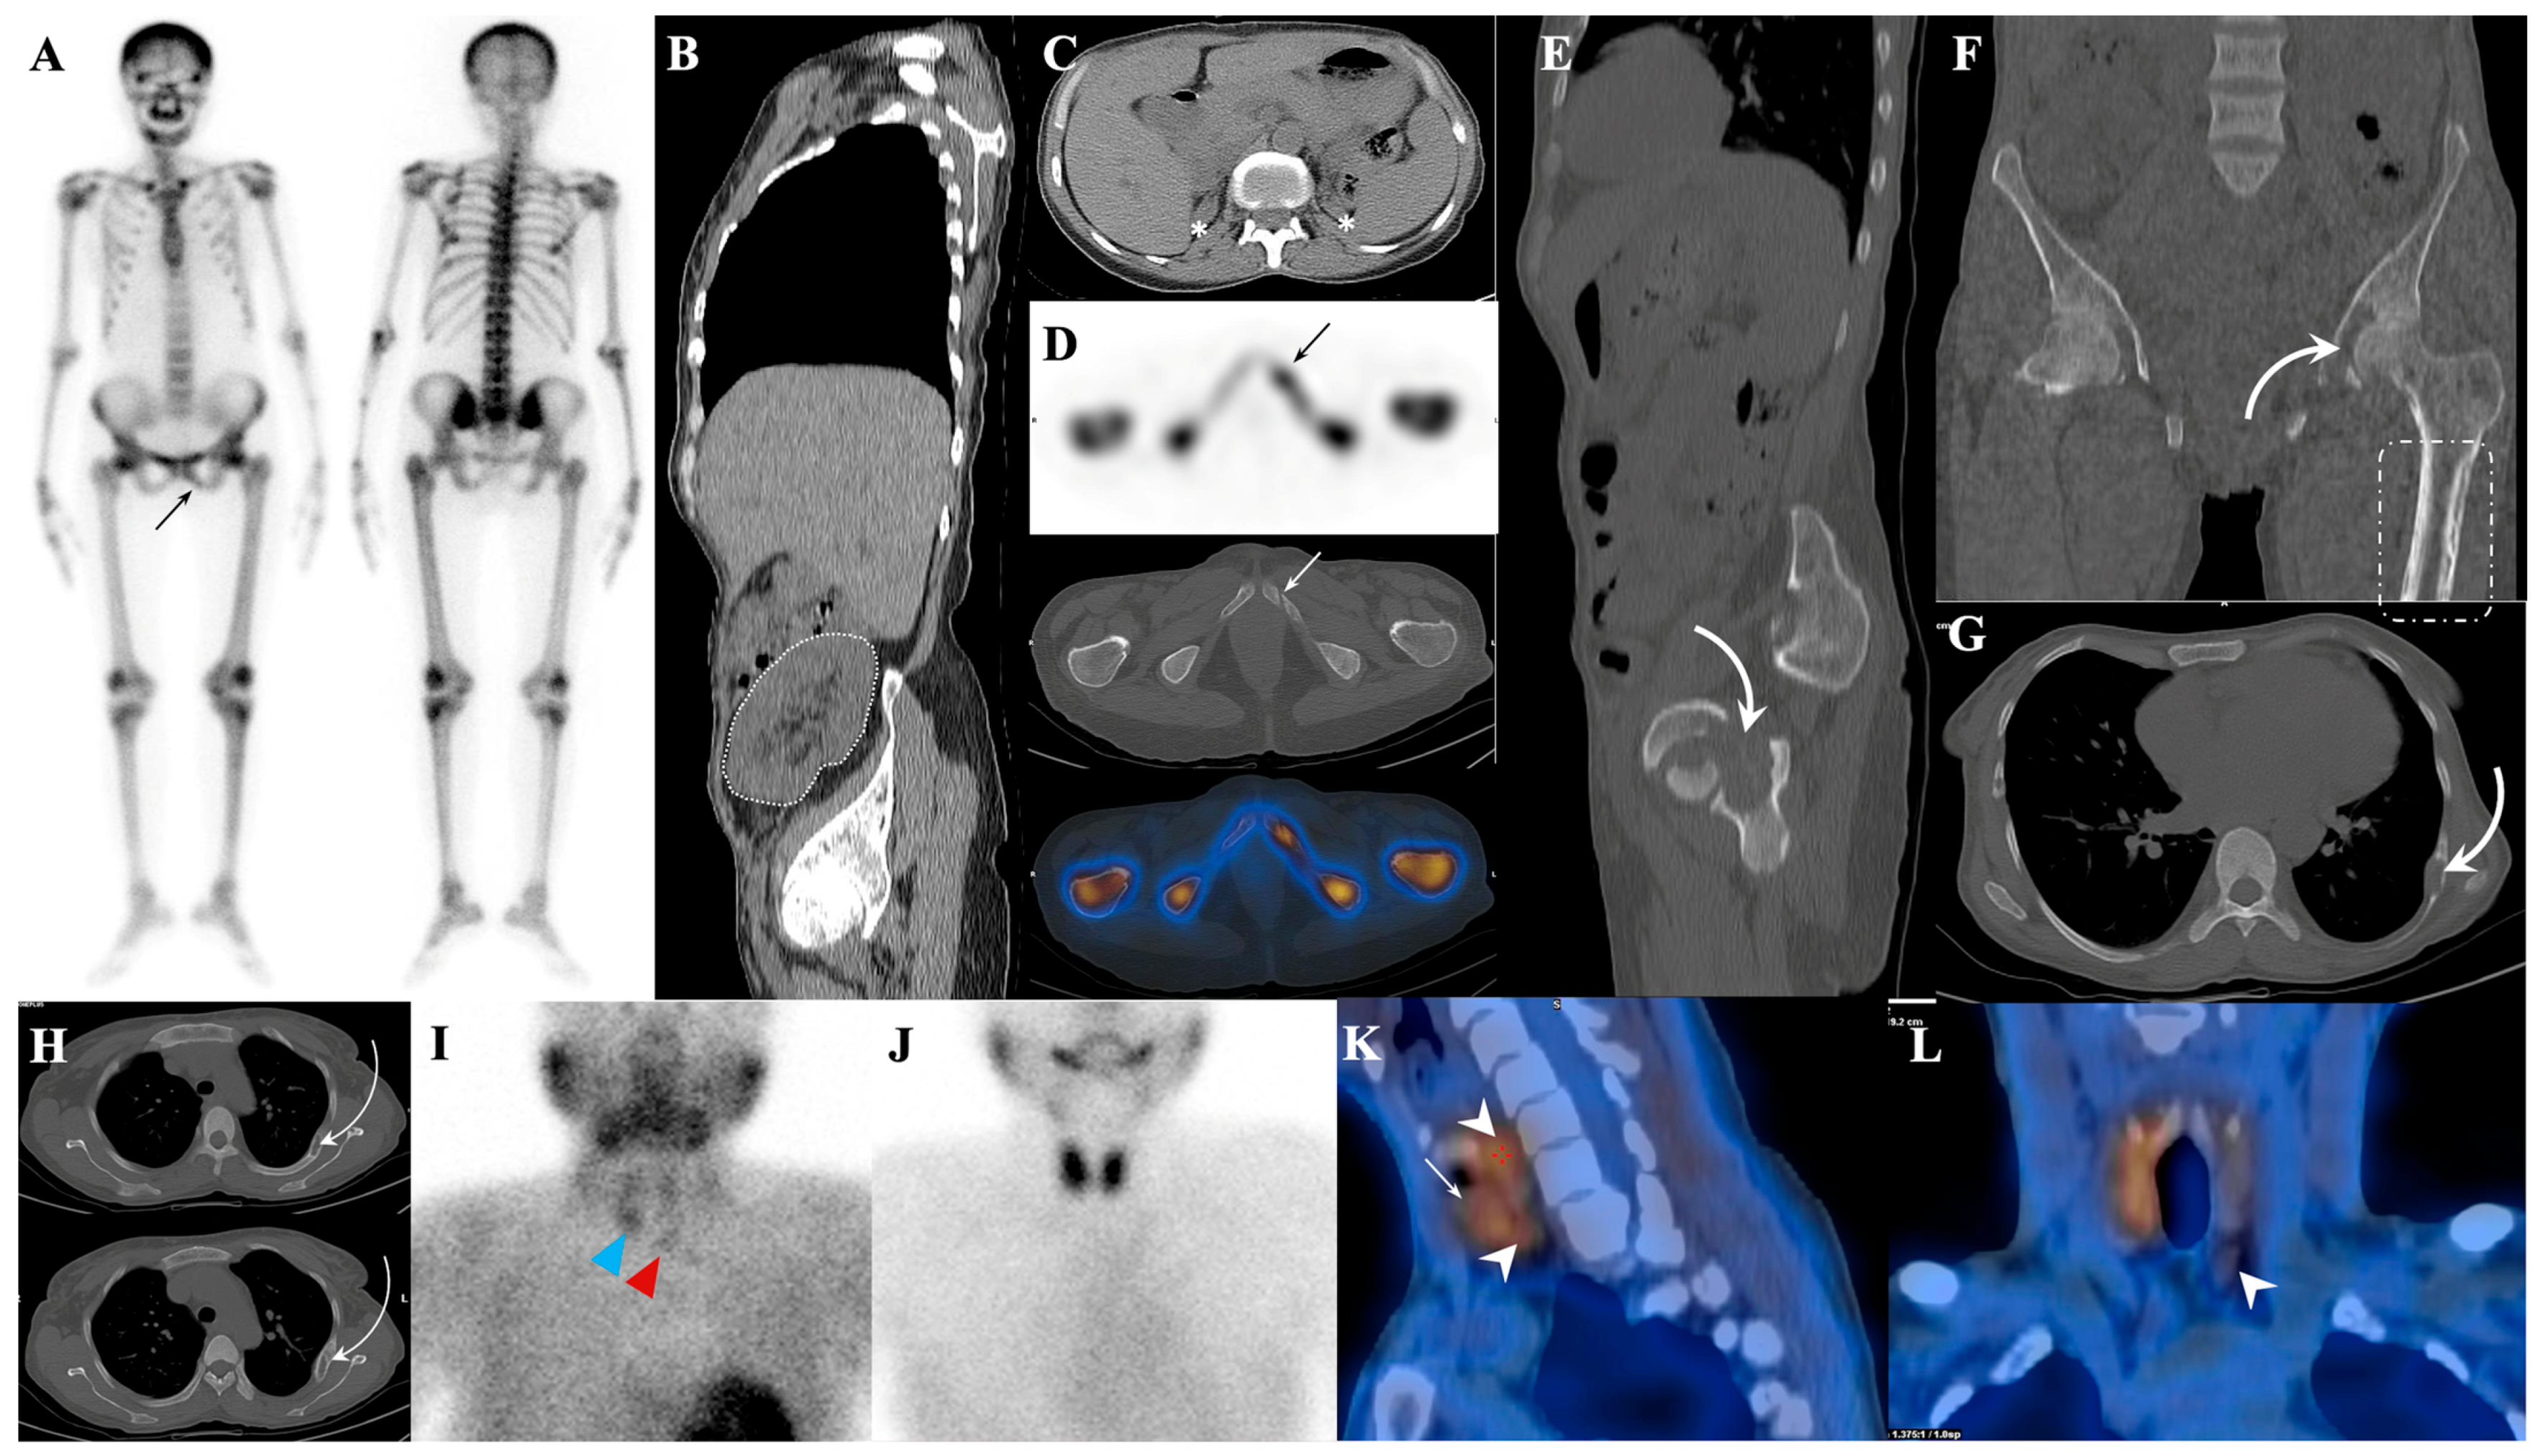

7.1.1. Superscan Pattern in Patients with Prostate Cancer

7.1.2. Dynamic Changes in Prostate Cancer Patients with Superscan